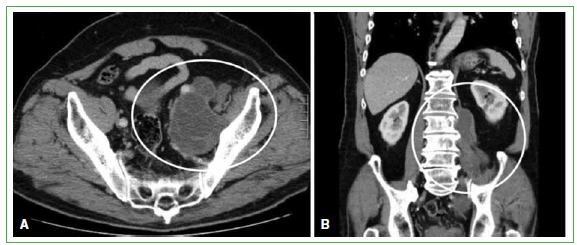

Paciente de 54 años, sin antecedentes mórbidos al comienzo del cuadro. Originario de una zona endémica del sur de Chile. Consulta, en marzo de 2008, en el Servicio de Traumatología de un hospital cercano, por un cuadro de dolor lumbar de 10 años de evolución, de carácter progresivo y persistente, asociado a una masa paravertebral lumbar palpable, de consistencia gomosa de aproximadamente 10 x 4 x 3 cm. Se realiza una tomografía computarizada que describe un proceso expansivo de partes blandas paravertebrales posteriores a derecha, con compromiso erosivo de la articulación interapofisaria L4-L5. La resonancia magnética muestra un proceso expansivo extrarraquídeo lumbar con extensión paravertebral y estenorraquis segmentaria de L4 a S1. Mide 14 x 6 x 5 cm con lobulaciones y límites bien definidos. Se toma una muestra por punción y el informe indica: muestra constituida por fibras musculares normotípicas acompañadas de material mucoide y elementos inflamatorios crónicos que incluyen células gigantes de tipo cuerpo extraño. El paciente es derivado al Hospital Base de Valdivia para continuar con el estudio de la masa paravertebral lumbar (Figura 4).

Figura 4.

Tomografía computarizada de abdomen y pelvis. A. Corte transversal. Se observa una lesión paravertebral derecha en relación con la articulación sacroilíaca. B. Corte coronal. Se visualiza una masa paravertebral de L4 a S1 derecha. (Agosto de 2009).